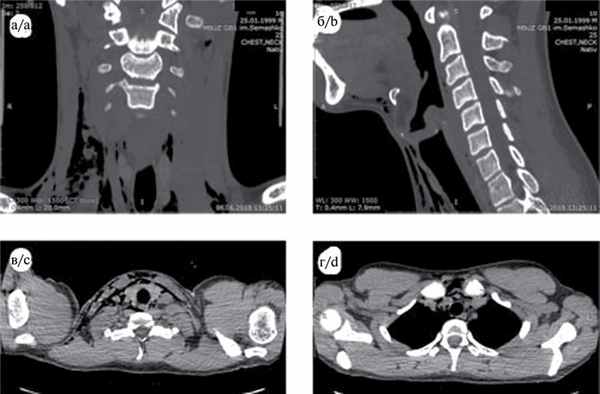

06.06.18 больному произведена КТ шеи и органов грудной клетки по программе спирального сканирования (СКТ) с толщиной среза 0,62 мм с последующей реконструкцией через 3 мм, без контрастного усиления. На серии аксиальных томограмм: органы шеи и гортань расположены обычно. Лимфоузлы шеи не увеличены. Нарушения целостности хрящей гортани и трахеи, подъязычной кости и позвонков не выявлено. В мягких тканях шеи и в верхнем отделе переднего средостения имеется скопление воздуха (рис. 1). Рис. 1. СКТ в коронарной (a), сагиттальной (б) и аксиальной (в, г) проекциях выявляет наличие воздуха в мягких тканях шеи, преимущественно справа, и в верхнем отделе переднего средостения. Очаговых или инфильтративных изменений легочной ткани не выявлено. Легочный рисунок умеренно усилен за счет расширения сосудов. Заключение: эмфизема мягких тканей шеи и верхних отделов переднего средостения.

Больному назначена антибактериальная терапия: ампициллина сульбактам 1,5 г 2 раза в день внутривенно, метронидазол 0,5% 100,0 внутривенно 3 раза в день, амикацин 500 мг 3 раза в день внутримышечно, инфузионная терапия. Все последующие дни отмечалась положительная динамика, уменьшение распространения подкожной эмфиземы, показатели крови нормализовались. На СКТ от 13.06.18 воздуха в мягких тканях шеи и средостения не обнаружено (рис. 2). Рис. 2. СКТ органов шеи (a — в коронарной, б — в сагиттальной проекции) и средостения (в — аксиальная проекция на уровне щитовидной железы, г — на уровне грудиноключичных сочленений). Воздух в мягких тканях шеи в основном не определяется. Имеется небольшое скопление воздуха в подкожной клетчатке по передней поверхности шеи, на уровне щитовидной железы. 14.06.18 больной выписан в удовлетворительном состоянии.